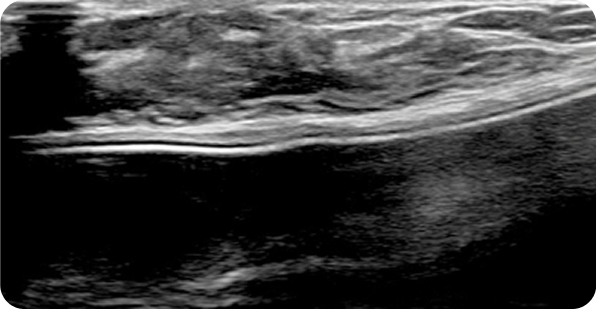

초음파 보면서

맘모톰도 안전하게